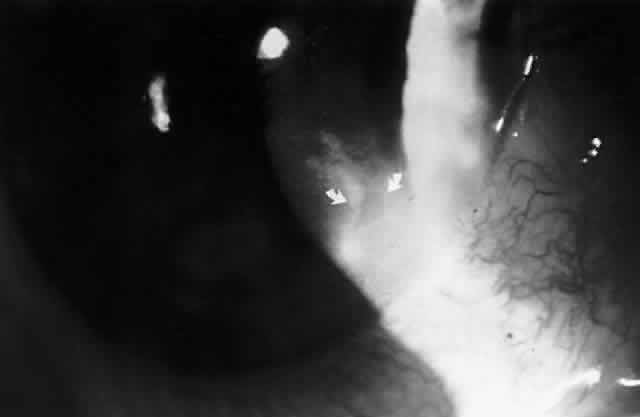

CONJUNCTIVA AND CORNEA There is increasing clinical and laboratory evidence suggesting that EBV is capable of infectingsusceptible cells in the ocular surface epithelia. Expression of CD21, the putative EBV receptor, has been detected in conjunctival and corneal epithelial cells.65 EBV genomic sequences have been detected in 10% of normal corneal epithelial specimens.30 Using highly sensitive reverse transcriptase PCR, EBNA-1 mRNA sequences, but not active latent or lytic cycle associated gene sequences, were detected in 95% of human conjunctival epithelial specimens obtained by impression cytology.31 Taken together, these results suggest that the ocular surface epithelia are sites of EBV persistence following primary infection. Numerous cases of conjunctivitis occuring in patients with IM syndrome were reported prior to the availability of specific tests to confirm a clinical diagnosis of IM.66 More recently, conjunctival involvement has been reported in patients with serologically confirmed IM. In 1981, Meisler and associates reported a case of a unilateral conjunctival inflammatory mass and enlarged preauricular lymph node in an 11-year-old boy with acute IM.67 The conjunctival lesion was biopsied, and an intense lymphocytic infiltrate with occasional multinucleated giant cells was observed in histologic sections. Wilhelmus reported a case of unilateral keratoconjunctivitis in a 16-year-old girl with acute IM.68 This patient had a follicular conjunctivitis and preauricular lymph node. Virus was cultured from the tears and conjunctiva of this patient. Matoba and associates also noted conjunctival inflammation consisting of mild hyperemia occasionally accompanied by a follicular tarsal conjunctival response in a series of patients with IM.69 Gardner and co-workers recently reported a case of a bulbar conjunctival nodule associated with unilateral enlarged preauricular and submandibular lymph nodes in a 38-year-old patient with acute IM. Mature lymphocytes and plasma cells were noted in histologic section, and scattered cells in the lesion stained positively for EBV active latent cycle antigens (LMP-1 and EBNA-2).70 The first reported association between IM and keratitis came from Payrau and Hoel in 1958.71 The authors described a patient with IM, follicular conjunctivitis, and in a single quadrant of one cornea, interstitial infiltrative keratitis. However, theputative association between IM and corneal stromal inflammation in their case is in doubt, because they also found a corneal foreign body within the area of keratitis. In 1980, Pinnolis and colleagues described a 16-year-old boy with classical heterophil antibody-positive (IM) who, upon discontinuation of oral corticosteroids, developed bilateral “nummular interstitial keratitis” without stromal vascularization.72 The corneal opacities were bilateral and symmetric unlike herpes simplex (HSV) and varicella-zoster virus-induced disease, and deeper within the corneal stroma than the subepithelial infiltrates of adenovirus keratitis. Acute and convalescent serologies by indirect immunofluorescence for specific antibody against EBV capsid antigen showed a greater than fourfold rise consistent with acute infection, while antibody titers by complement fixation for HSV, adenovirus, mumps, cytomegalovirus, influenza virus, and respiratory syncytial virus remained low or undetectable throughout the illness. In 1986, Matoba and associates reported 7 patients with purported EBV stromal keratitis, but only 3 of the patients had clinical symptoms of IM or evidence of recent seroconversion.69 In one of the patients, heterophil antibody-positive IM preceded by 1 week the onset of chronic multifocal keratitis. When the authors first examined the patient in referral 9 months later, they found multiple, discrete, anterior stromal opacities in the patient's left eye. In another patient, bilateral, patchy, deep peripheral infiltrative keratitis and a fourfold decrease in antibody against EBV viral capsid antigen were documented at the time of referral 5 months after an “infectious mononucleosis-like illness” associated with bilateral red eyes and photophobia. In another patient, the authors state that IM preceded subepithelial infiltrative keratitis in the left eye by 1 month. When examined 8 months after onset of the keratitis, the patient's left cornea showed features of multifocal anterior stromal and deep peripheral stromal keratitis. Although the other 4 patients in this series did not show evidence of recent EBV seroconversion, their keratitis appeared similar to that of the patients with documented IM. On clinical grounds alone, Matoba and associates postulated that the development of EBV keratitis did not depend on recent EBV infection, but could occur in the chronic carrier state. To summarize the authors' findings in the combined group of 7 patients, the interstitial keratitis appeared in 4 patients as unilateral, multifocal, discrete, sharply demarcated, anterior stromal opacities, 0.1 to 2 mm in diameter, with either a blotchy pleomorphic (Fig. 2) or granular ringlike appearance (Fig. 3), in two patients as bilateral, multifocal, full-thickness or deep stromal peripheral infiltrates reminescent of luetic keratitis (Fig. 4), and in 1 patient with features of both. No patient tested had showed serologic evidence of acute systemic HSV or adenovirus infection. Both patients with keratitis restricted to the peripheral cornea had bilateral disease but lacked serologic evidence for syphilis (nonreactive MHA-TP). Five patients had mild or moderate corneal stromal vascularization. Two patients showed corneal epithelial granularity overlying the stromal opacities.

In a second report, Matoba and Jones described two additional patients with subepithelial corneal infiltrates similar to those seen in adenoviral epidemic keratoconjunctivitis.73 One patient showed a greater than fourfold rise in antibody against EBV nuclear antigen. Serum antibodies to adenovirus were not detected in either patient. In 1990, Pflugfelder and associates reported a 66-year-old woman with bilateral, pleomorphic, ring-shaped, anterior stromal opacities which developed 3 months after initial onset of concurrent bilateral, dendritic epithelial keratitis (Fig. 5).74 Dendritic epithelium removed by impression cytology at the second recurrence of epithelial disease bound monoclonal antibody to EBV early antigen-diffuse and contained EBV genomic sequences as shown by PCR. Corneal epithelial cultures for HSV were negative on two occasions. EBV serology test did not indicate acute infection, and thus confirmed the earlier impression of Matoba and associates, that EBV keratitis may follow viral reactivation from the chronic carrier state.